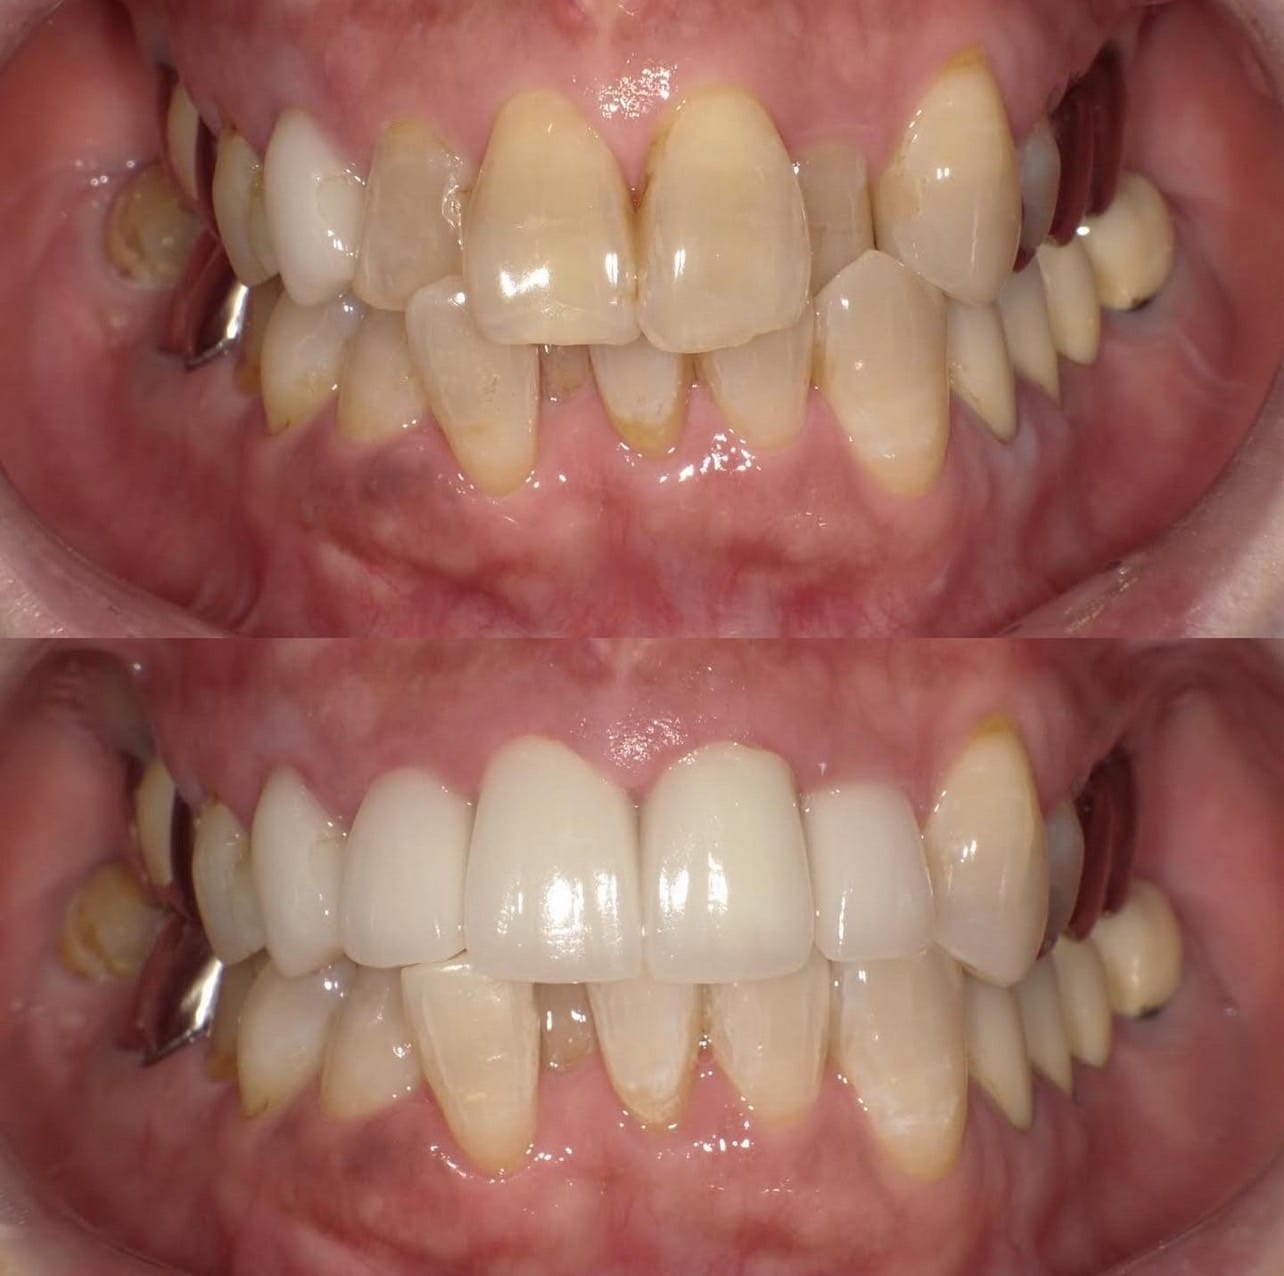

噛み合わせから審美的なところまで、トータルで治療させて頂いた患者様です。

ここまでやるとなると、できないクリニックもありますし、できるところでも年単位でかかってしまうクリニックが大半だと思いますが、今回は4月末にカウンセリングでご来院いただき、5月に治療をスタートして9月末には診療が終わっています。

治療回数や、治療期間がかかってしまうと、患者様も通院が辛くなったり疲れてしまったりしてしまうと思います。どんどん綺麗になっていく、食事がしやすくなっていくという実感がある方が患者様に楽しく治療に臨んでいただけると思うので、私は診療のスピード感を大切にしています。

トータルでやらせていただいたので、噛み合わせなどの機能面から外見などの審美性もかなり良くなり、患者様にも満足して頂けてよかったです。

治療期間 約4ヶ月